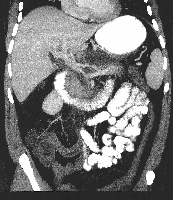

Πρόκειται για άνδρα ασθενή 41 ετών που διαπιστώθηκε να πάσχει από επιμολυσμένο παγκρεατικό νέκρωμα (infected Walled-Off Necrosis – WON), το οποίο αναπτύχθηκε ως μετεξέλιξη επεισοδίου χολολιθιασικής νεκρωτικής παγκρεατίτιδας. Η παγκρεατική νέκρωση (ποσοστό > 70%) προκαλούσε στένωση της πυλαίας με συνοδό διάταση της στεφανιαίας φλέβας (εικόνα 1). Υποβλήθηκε στις νεκροσεκτομή, επιπλοοπλαστική και χολοκυστεκτομή. Κατά τη διάρκεια της επέμβασης διαπιστώθηκε νέκρωση στην κεφαλή, το σώμα και την ουρά του παγκρέατος (εικόνα 2). Η περιοχή εκπλύθηκε με τη χρήση Simpulse Suction/Irrigation System (Stryker) και 6 lt RL (εικόνα 3). Τοποθετήθηκαν παροχετεύσεις στον ελάσσονα επιπλοϊκό θύλακο, στη δεξιά και αριστερή κολική αύλακα (εικόνα 4). Πραγματοποιήθηκε επιπλοοπλαστική κατά Farkas (εικόνα 5). Τα παρασκευάσματα (παγκρεατικά νεκρώματα, τμήμα του μείζονος επιπλόου και χοληδόχος κύστη) παρουσιάζονται στην εικόνα 6. Ο ασθενής έλαβε εξιτήριο τη 18η μετεγχειρητική ημέρα, στιζόμενος κανονικά, χωρίς πόνο και με φυσιολογικές εργαστηριακές τιμές (λευκά αιμοσφαίρια, αμυλάση ορού, κτλ).